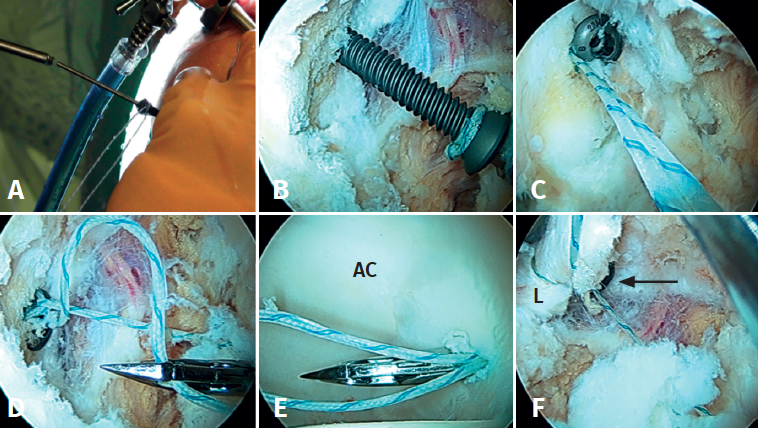

(A4) Osificación circunferencial completa del labrum contiguo al borde lateral del borde acetabular

- Características y morfología radiográfica: osificación circunferencial del labrum, menos redondeada y contigua con el borde lateral del borde acetabular. No tiene línea radiolúcida medial, a diferencia de las otras calcificaciones descritas previamente. La tomografía axial computarizada (TAC) revela el “signo de doble borde” del acetábulo y la imagen tridimensional de la reconstrucción por TAC revela un engrosamiento del borde acetabular, hallazgos que orientan a la osificación del labrum. Estos pacientes tienen un excelente mantenimiento del espacio articular y del cartílago articular (al menos 2 mm de espacio articular en las radiografías) y ningún daño o daño de bajo grado del cartílago en la artroscopia. La falta de osteofitos o degeneración articular avanzada apoya la afirmación de que este tipo de osificación es un proceso separado de los osteofitos acetabulares(5)(Figura 5).

- Localización y lesiones asociadas: estos pacientes representan un subgrupo de CFA de tipo pincer, generalmente anterolateral y tienen más probabilidades de ser mayores, mujeres y tener síntomas más graves(5).

- Tratamiento: la cirugía (abierta o artroscópica) se puede utilizar para la escisión de este tipo de calcificación con una expectativa razonable de mejoría de los síntomas. En casos de remanente labral, este es separado cuidadosamente del resto de la porción osificada mediante uso de bisturí artroscópico o radiofrecuencia. A continuación, se procede a la extirpación de la porción osificada del labrum (acetabuloplastia) con una fresa de 5,5 mm y finalmente, si el resto labral es suficiente, se procede a su reparación. Habitualmente y debido al daño importante o la funcionalidad escasa del labrum tras la extirpación, en nuestra experiencia asociamos generalmente la técnica de aumento o de reconstrucción labral(6).